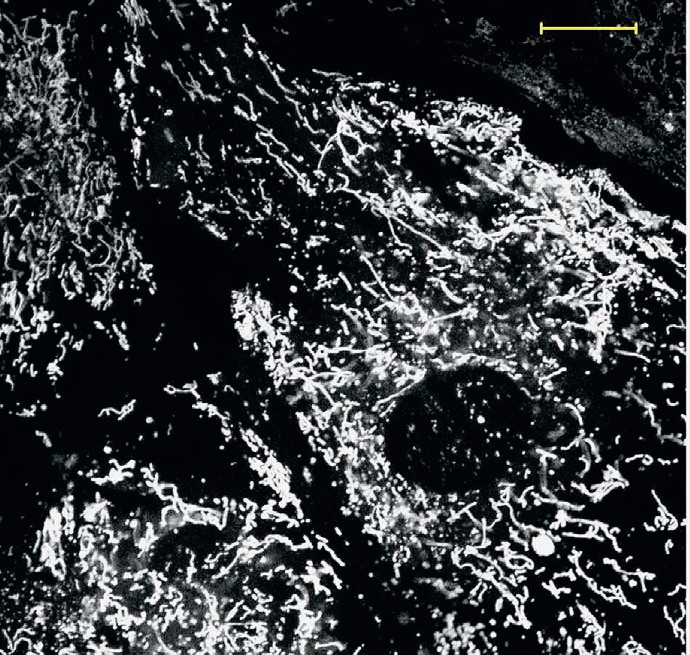

Сотрудники МГУ им. М. В. Ломоносова для лечения почечной недостаточности новорождённых испытали антиоксидант SkQR1. Сепсис у новорождённых крысят моделировали с помощью инъекции липополисахарида клеточной стенки бактерий. Вооружившись электронным микроскопом, исследователи обнаружили, что основные структуры, страдающие при действии липополисахарида,